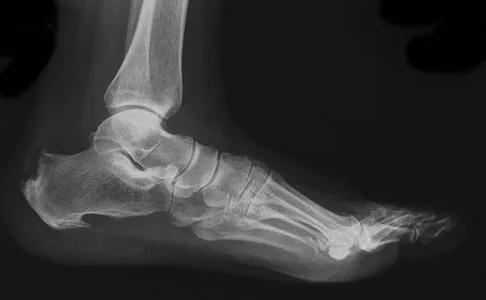

A 42-year-old woman sustained a closed, displaced talar neck fracture in a motor vehicle accident. Which of the following is an avoidable complication of surgical treatment?

Malunion of the talus is a devastating complication that leads to malpositioning of the foot and subsequent arthrosis of the subtalar joint complex. This is considered an avoidable complication in that accurate surgical reduction will minimize its development. Posttraumatic arthritis of the subtalar joint, osteonecrosis of the talus, posttraumatic arthritis of the ankle joint, and complex regional pain syndrome all may develop as a result of the initial traumatic event and may not be avoidable despite anatomic reduction. Rockwood and Green's Fractures in Adults, ed 5. Philadelphia, PA, Lippincott, Williams and Wilkins, 2001, pp 2091-2132.

- Daniels TR, Smith JW, Ross TI: Varus malalignment of the talar neck: Its affects on the position of the foot and on subtalar motion. J Bone Joint Surg Am 1996;78:1559-1567.